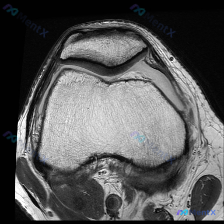

今天看到一个很有代表性的读片问题,整理出来和大家分享讨论:问题是判断这张髌股关节轴位T1加权MRI上有没有软骨异常,我们一步步梳理思路。 一、先看影像基本信息 这是一张膝关节MRI的轴位T1加权图像,扫描层面位于膝关节上方的髌股关节层面: 1. 骨骼结构:髌骨位于前方,骨皮质边缘清晰,骨髓脂肪信号正...

刚看到这个有意思的影像病例,整理一下完整资料和分析思路给大家参考。 病例基本信息 这是一张膝关节MRI T1加权轴位扫描影像,核心问题是:临床提示存在「软骨异常」,需要解读影像表现并分析原因。 影像客观评估结果 先给大家说客观的影像发现: 1. 骨性结构:股骨远端滑车、髌骨的骨皮质完整,松质骨髓信号...